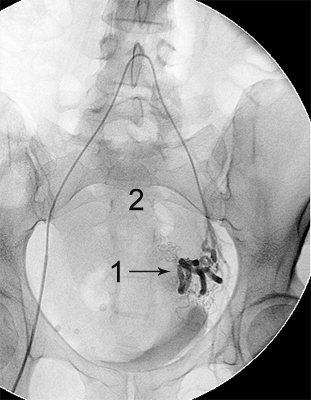

Ангіограми до та після емболізації:

міома матки до емболізації    міома матки після емболізації

Розширена звивиста ліва маткова артерія (1),

вузол лейоміоми матки (2)